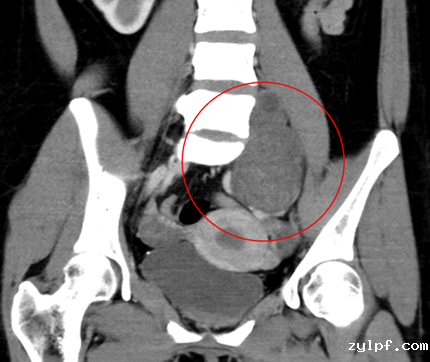

患者21岁女性,因左下腹隐痛2月,检查发现左腰骶椎前占位4天来诊。入院后进一步完善影像学检查提示左侧L5/S1椎间孔及椎体前后方占位。病灶钻缝生长,延伸至椎管内,再沿L5左侧横突孔向后伸至脊柱旁,横突孔增宽增大,骨质变薄,邻近肠管、左侧髂总血管稍推压移位。穿刺活检结果提示神经鞘瘤。

图片 7.png

图片 8.png

因肿瘤成哑铃状跨越椎体前后方,手术需行前后联合入路,前方入路需面对髂血管、输尿管等重要结构,后方则有脆弱的脊髓及神经根,对手术技巧要求极高,并且需要手术医生掌握大量的解剖学知识。经过充分的术前准备及术中的精细操作,完整切除肿瘤并重建脊柱稳定性。术后患者下肢功能未受影响,复查腰椎正位片示内固定稳定在位,CT示肿瘤已完整切除。